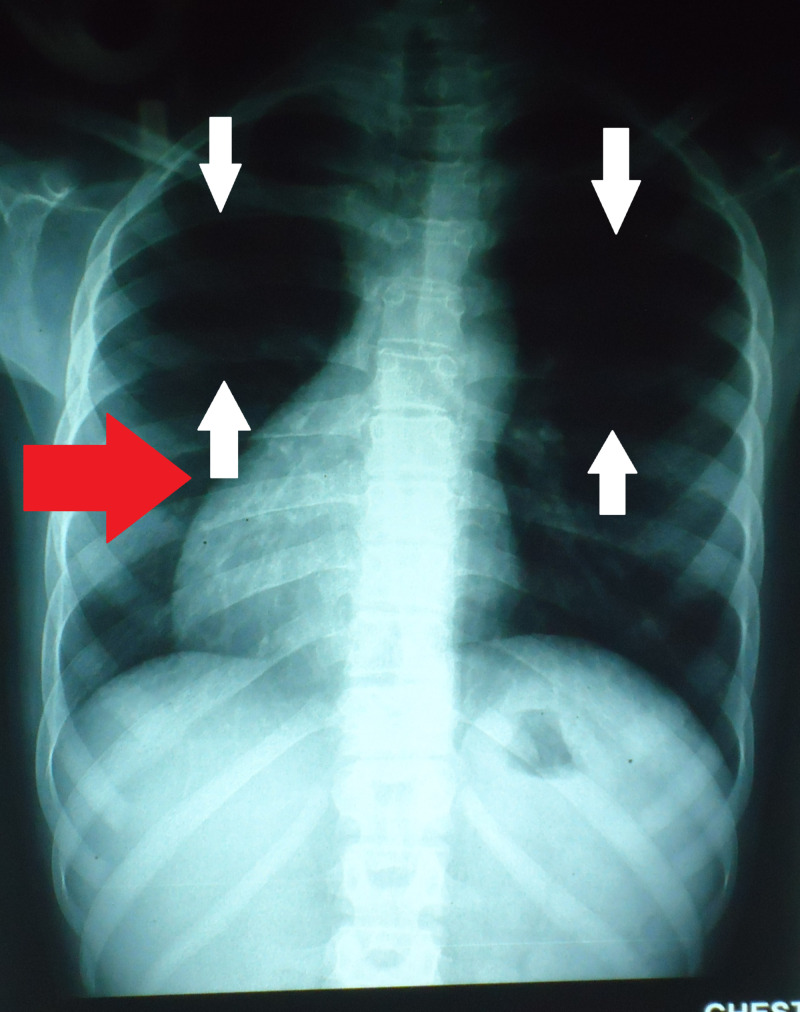

Figure 1 shows a chest radiograph of posteroanterior view with decreased right lung volume. The heart is also seen to be displaced to the right side as pointed by the red arrow.

Figure 1. Posteroanterior chest X-ray PA showing oligemic lung fields (see white arrows). The red arrow indicates dextrocardia.